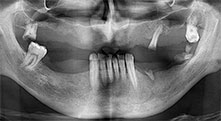

Bratu: Wir nutzen die Instrumente routinemäßig für die Entnahme von Knochenblöcken und das Spalten von Kieferkämmen. Weiterhin osteotomieren wir mit den Piezomed B6/B7 retinierte Zähne und entfernen nicht erhaltungsfähige Implantate. Alles Indikationen, bei denen es auf tiefe, saubere Schnitte ankommt.

Bratu: Wir bevorzugen Knochenentnahmen von der Linea obliqua externa des posterioren Unterkiefers, nicht aus der interforaminalen Region. Nach der Weichgewebsinzision verwenden wir die neuen Sägen, um den Umfang der Knochenentnahme zu definieren. Wir erledigen damit in fast 80 Prozent der Fälle auch die gesamte Präparation. Zusätzlich verwenden wir eventuell andere Piezo-Instrumente und zuletzt einen Meißel, um den Block zu mobilisieren. Das ist für uns eine sehr effektive Operationstechnik.

Bratu: Ich halte Piezo für einen großen Sprung nach vorn für die Oralchirurgie. Die Technik macht Knochenpräparationen sicherer und leichter. Man verliert wenig Knochen, zum Beispiel bei Extraktionen. In der ästhetischen Zone ist dies sehr wichtig, vor allem wenn eine Sofortimplantation geplant ist. Auch für Weichgewebe ist Piezochirurgie ein Sicherheitsgewinn: Membranverletzungen in der Kieferhöhle sind im Prinzip Geschichte, ebenso Nervverletzungen bei Knochenblockentnahmen. Es gibt auch Daten, die geringere postoperative Schwellung und Beschwerden zeigen. Übrigens lassen sich mit Piezochirurgie auch sehr gut Kieferhöhlensepten präparieren. Nicht zuletzt profitieren unsere Patienten von der schonenden Arbeitsweise dieser Technik.